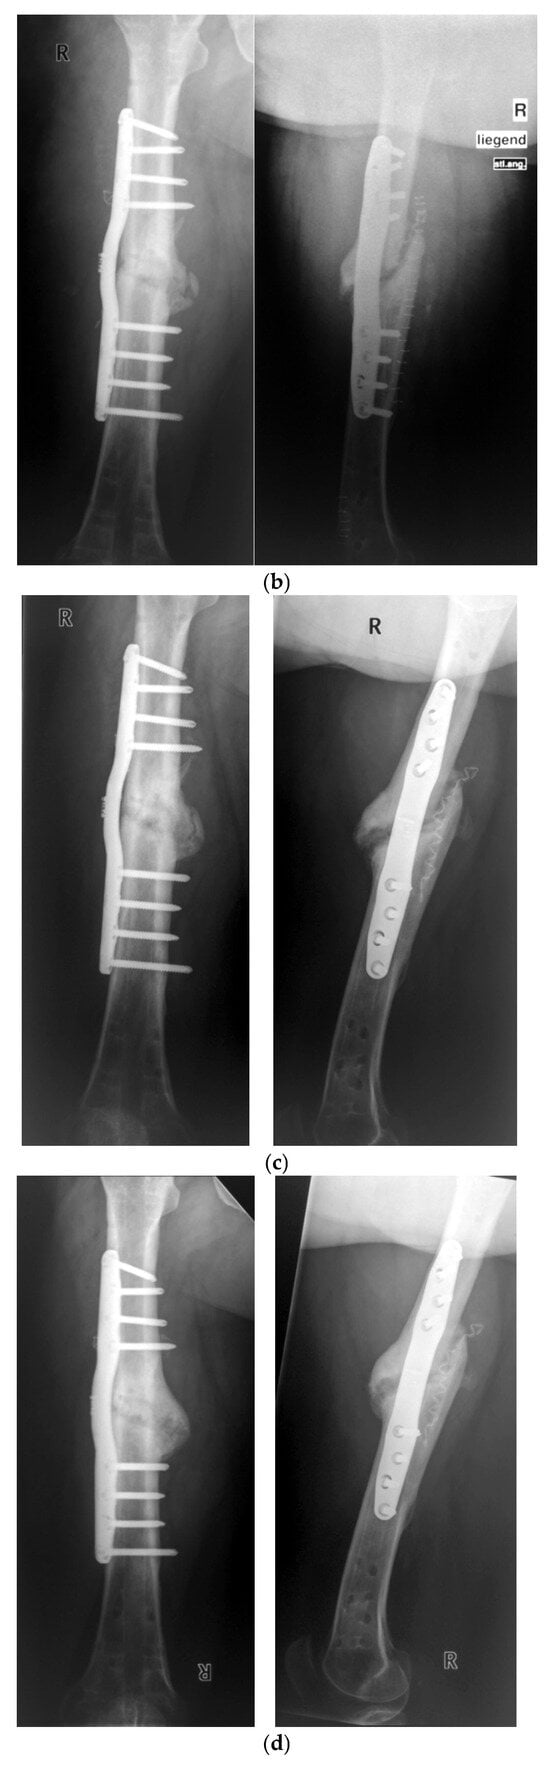

Long-Term Evaluation of Bone Healing Monitoring Using an Instrumented Plate with Measurement Sensors (Smart Implant) over 10 Years

by Arndt P. Schulz, Birgitt Kowald, Matthias Münch, Klaus Seide, Nils Weinrich, Tobias Barth and Benjamin Kienast

Sensors 2025, 25(18), 5779; https://doi.org/10.3390/s25185779 - 16 Sep 2025

A total of 66 smart implants were included. As a measure of bony stability, the relative elastic compliance of the osteosynthesis was determined from the gradient between the applied external load and the measured implant load over the entire healing process. The healing [...] Read more.

A total of 66 smart implants were included. As a measure of bony stability, the relative elastic compliance of the osteosynthesis was determined from the gradient between the applied external load and the measured implant load over the entire healing process. The healing process of non-unions of the femur with a smart implant was tracked by telemetric measurements over a timespan of up to 10 years. The measurements of the longest healing process show a very slow but constant decrease in force transmission over the implant, radiological findings over 10 years show corresponding consolidation until bony healing. The use of a telemetrically instrumented bone plate, a so-called smart implant, to monitor the healing process is a successful procedure to support the clinician in his decision to take further surgical measures or to wait until healing occurs. Full article